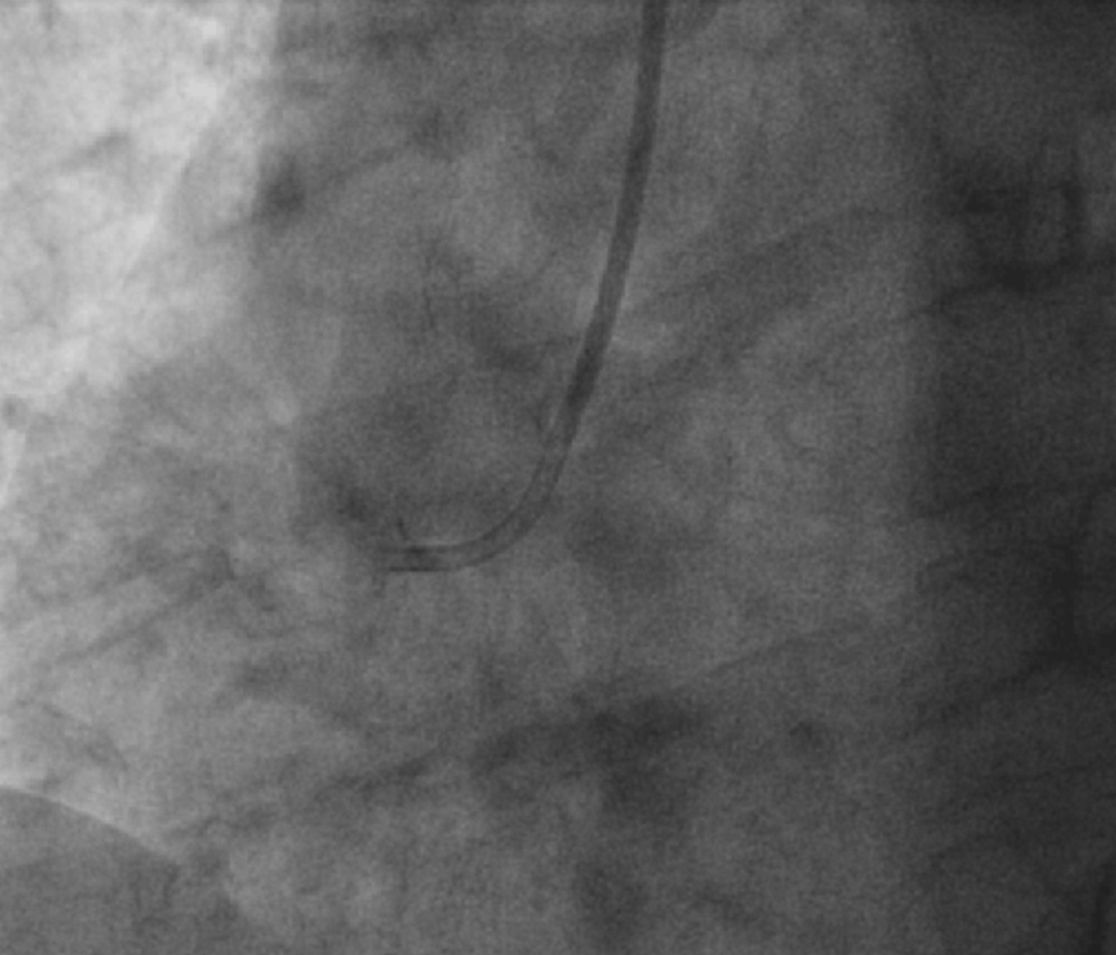

Die Koronarangiographie und –intervention ist ein Meilenstein in der Diagnostik und Therapie der koronaren Herzerkrankung. Engstellen und Verschlüsse in den Herzkranzgefäßen, die Beschwerden von Angina pectoris  bis hin zu einem Herzinfarkt  auslösen können,  werden präzise dargestellt und in gleicher Sitzung behandelt.  Das Spektrum der interventionellen Versorgung ist stetig gewachsen und reicht  in unserer Klinik von komplexen Eingriffen im Bereich des linkskoronaren Hauptstammes, über die Rotablation bei kalzifizierten subtotalen Stenosen und  der Lithotripsie (Shockwave©)  bis hin zur Wiedereröffnung  chronisch verschlossener Gefäße (CTO; chronic total occlusion).

Die Engstellen werden mittels Ballonkatheter  und Implantation von neuen medikamentenbeschichteten (Drug eluting) Stents beseitigt (bioresorbierbare Scaffolds bei entsprechender Indikation eingeschlossen).

Darüber hinaus werden zur Bewertung der koronaren Engstellen intravaskuläre Bildgebungen mittels intravaskulären Ultraschall (IVUS) oder optischer Kohärenztomographie (OCT) sowie Druckdrahtmessung  zur Bestimmung  der intravaskulären Flussreserve (FFR/iFR) regelmäßig angewendet.